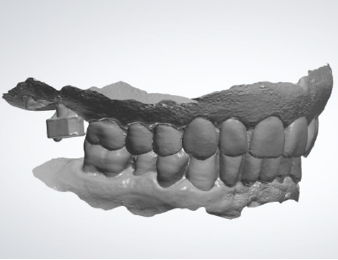

Figure 4A: Digital impression of the maxillary arch with the removable prosthesis in place and the scan bodies.

Figure 4B: Digital impression of the antagonist arch.

Figure 4C: Digital impression of the maxillomandibular relationship of patients’ habitual occlusion in maximum intercuspation.

After concluding the surgical phase, the implant scan bodies were connected to the implants and merged together with the universal scan template (Designed by Dr Andrea Papa, produced by LaStruttura S.p.A., Cassano Magnago, Italy), in order to ease the scanning procedure in case of altered or bleeding mucosa (Figure 5). The scan started from the skeletal scan bodies to allow the software to correlate the pre-surgucal and post-surgical scans obtaining a perfect relation with the opposing arch (Figure 6).

Figure 5: Post-surgical digital impression including the skeletal scan bodies, the implant scan bodies and the universal scan template.

Figure 6: Maxillo-mandibular relationship in patient’s habitual occlusion in maximum intercuspation obtained matching the pre-surgical and post-surgical digital scans.